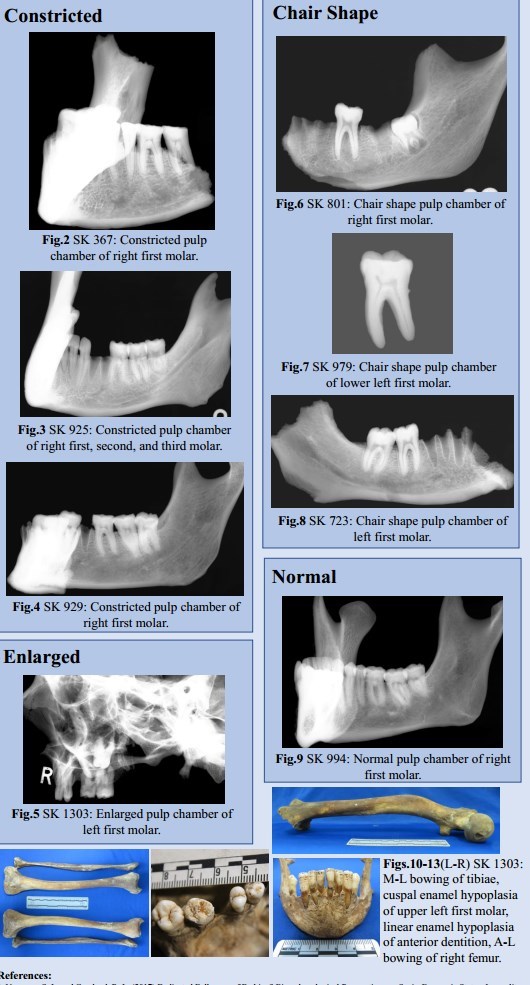

Only two of the 30 individuals had skeletal manifestations consistent with a diagnosis of residual rickets (abnormal bowing of the lower limbs) (1303, 1635).

SK1303 exhibited an enlarged pulp chamber. Clinically, this has been linked to both vitamin D- resistant hypophosphatemic rickets and odontogenesis imperfecta.6 This individual is currently the subject of further research, as they also exhibit skeletal change consistent with residual rickets (See Figs.10-13).